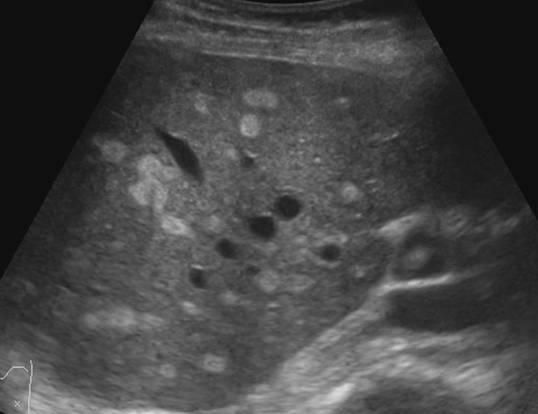

C

This one above turned out to be a hyatid cyst (Echinococcosis).